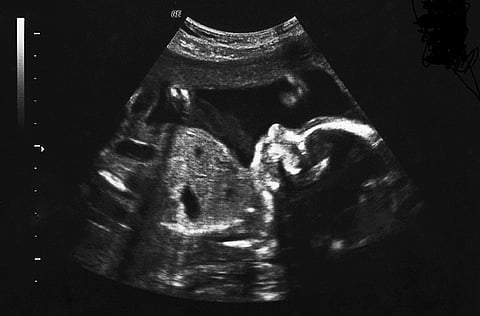

Clutching husband Rajesh*’s hand, 20-year-old Nilima* stares at a monitor displaying grainy black and white swirls. She’s 20 weeks pregnant and they’re in a small clinic in Jaipur, the capital of the western Indian state of Rajasthan, about to see an image of their unborn baby for the first time.

Her husband has his eyes glued to the monitor as the doctor examines the foetus’ heart and vital details to check it’s growth and health. But there’s one thing Rajesh, a businessman, wants to know more than anything else – the sex of their child.

When the scan is over, the doctor leads Rajesh and Nilima to his office where he gives them the news – their unborn baby is a girl. The disappointment on both the parents’ faces is evident. While Nilima’s eyes well up because she knows what her fate and that of her unborn child will be, Rajesh quietly takes the doctor to a corner of his office.